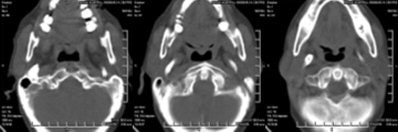

CT scan showed the presence of ossification of the right stylohyoid chain articulating with the hyoid bone. An elongated styloid process was present on the left side.